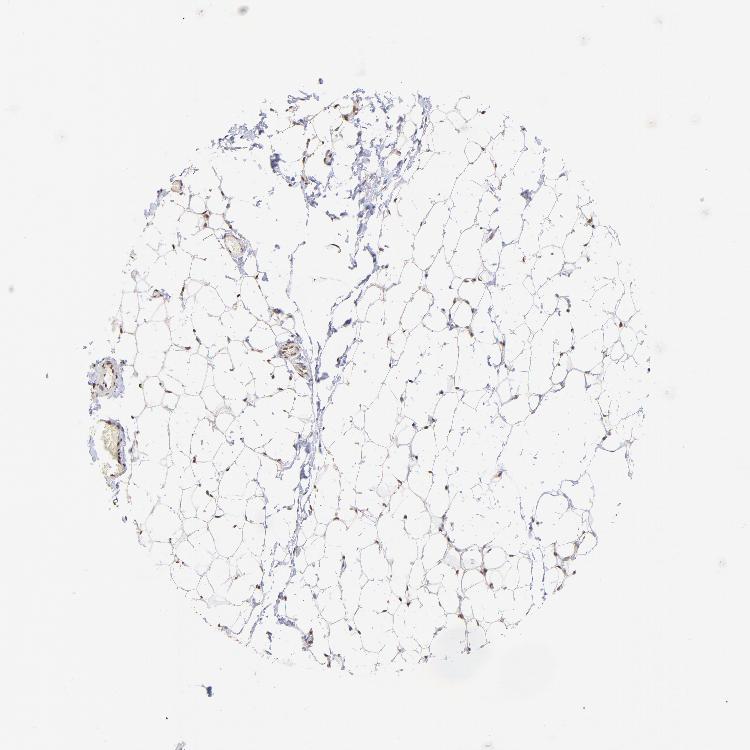

SOFT TISSUE 1 - Antibody stainingi

Antibody staining in the annotated cell types in the current human tissue is reported as not detected, low, medium, or high, based on conventional immunohistochemistry profiling in selected tissues. This score is based on the combination of the staining intensity and fraction of stained cells.

Each image is clickable and will lead to virtual microscopy that enables deeper exploration of all samples and also displays staining intensity scores, fraction scores and subcellular localization as well as patient and tissue information for each sample.

Antibody HPA003113

Chondrocytes Not detected

Fibroblasts High

Peripheral nerve High

SOFT TISSUE 2 - Antibody stainingi

Fibroblasts Medium

Peripheral nerve Medium